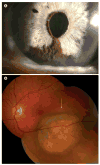

Uveal melanoma is the most common primary cancer of the eye, and often results not only in vision loss, but also in metastatic death in up to half of patients. For many years, the details of the molecular pathogenesis of uveal melanoma remained elusive. In the past decade, however, many of these details have emerged to reveal a fascinating and complex story of how the primary tumor evolves and progresses. Early events that disrupt cell cycle and apoptotic control lead to malignant transformation and proliferation of uveal melanocytes. Later, the growing tumor encounters a critical bifurcation point, where it progresses along one of two genetic pathways with very distinct genetic signatures (monosomy 3 vs 6p gain) and metastatic propensity. Late genetic events are characterized by increasing aneuploidy, most of which is nonspecific. However, specific chromosomal alterations, such as loss of chromosome 8p, can hasten the onset of metastasis in susceptible tumors. Taken together, this pathogenetic scheme can be used to construct a molecularly based and prognostically relevant classification of uveal melanomas that can be used clinically for personalized patient management.